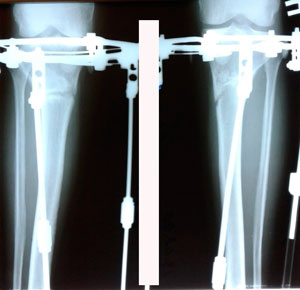

Дата операции - 17.10.2019г

Дата снятия аппаратов - 14.02.2020

Срок сращения - 117 дней.